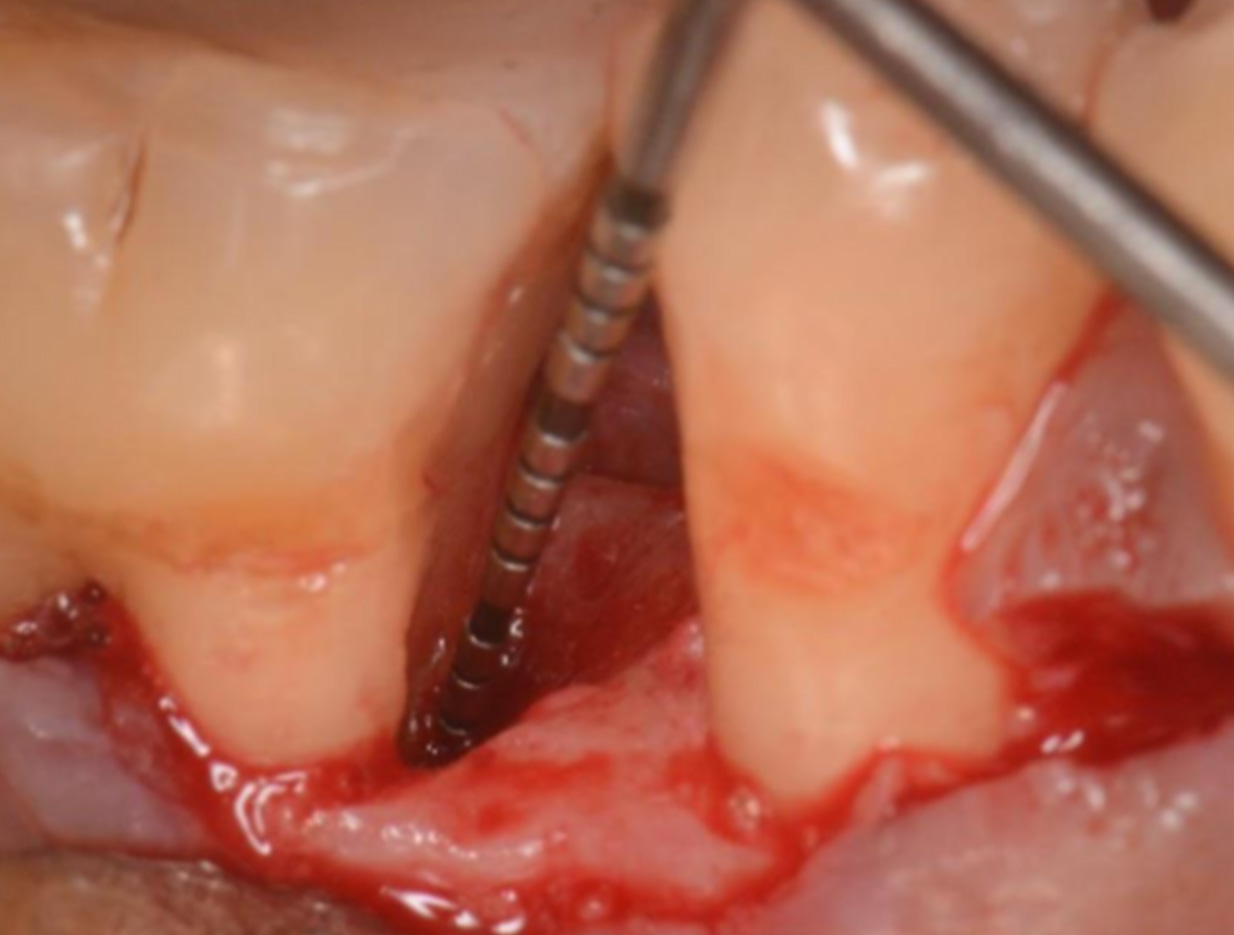

牙周病造成的牙骨流失

牙周再生手術前